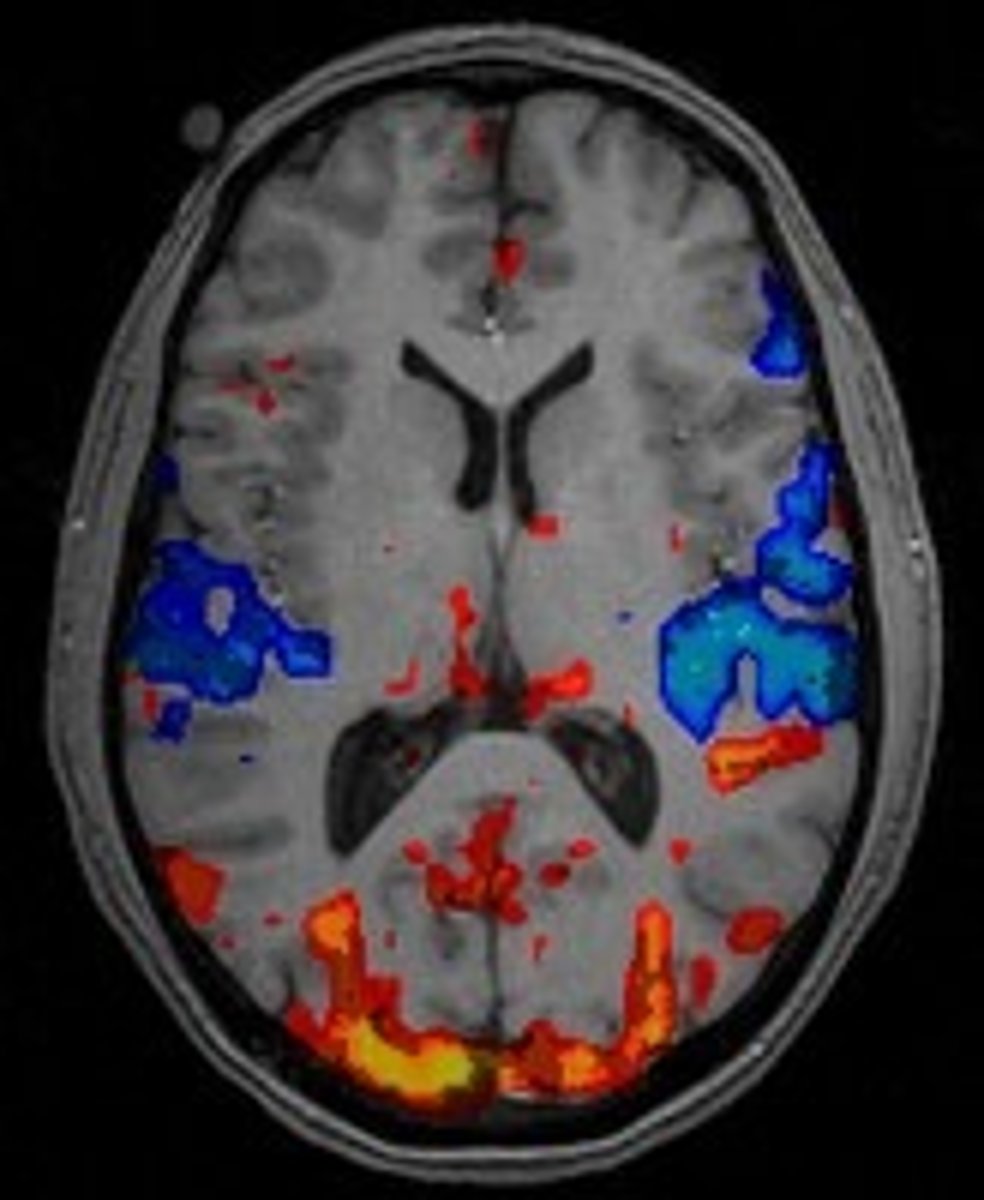

(fMRI) Functional MRI

technique for revealing blood flow and, therefore, brain activity by comparing successive MRI scans. These scans show brain functions as well as its structure.

(PET) positron emission tomography scan

a visual display of brain activity that detects where a radioactive form of glucose goes while the brain performs a given task